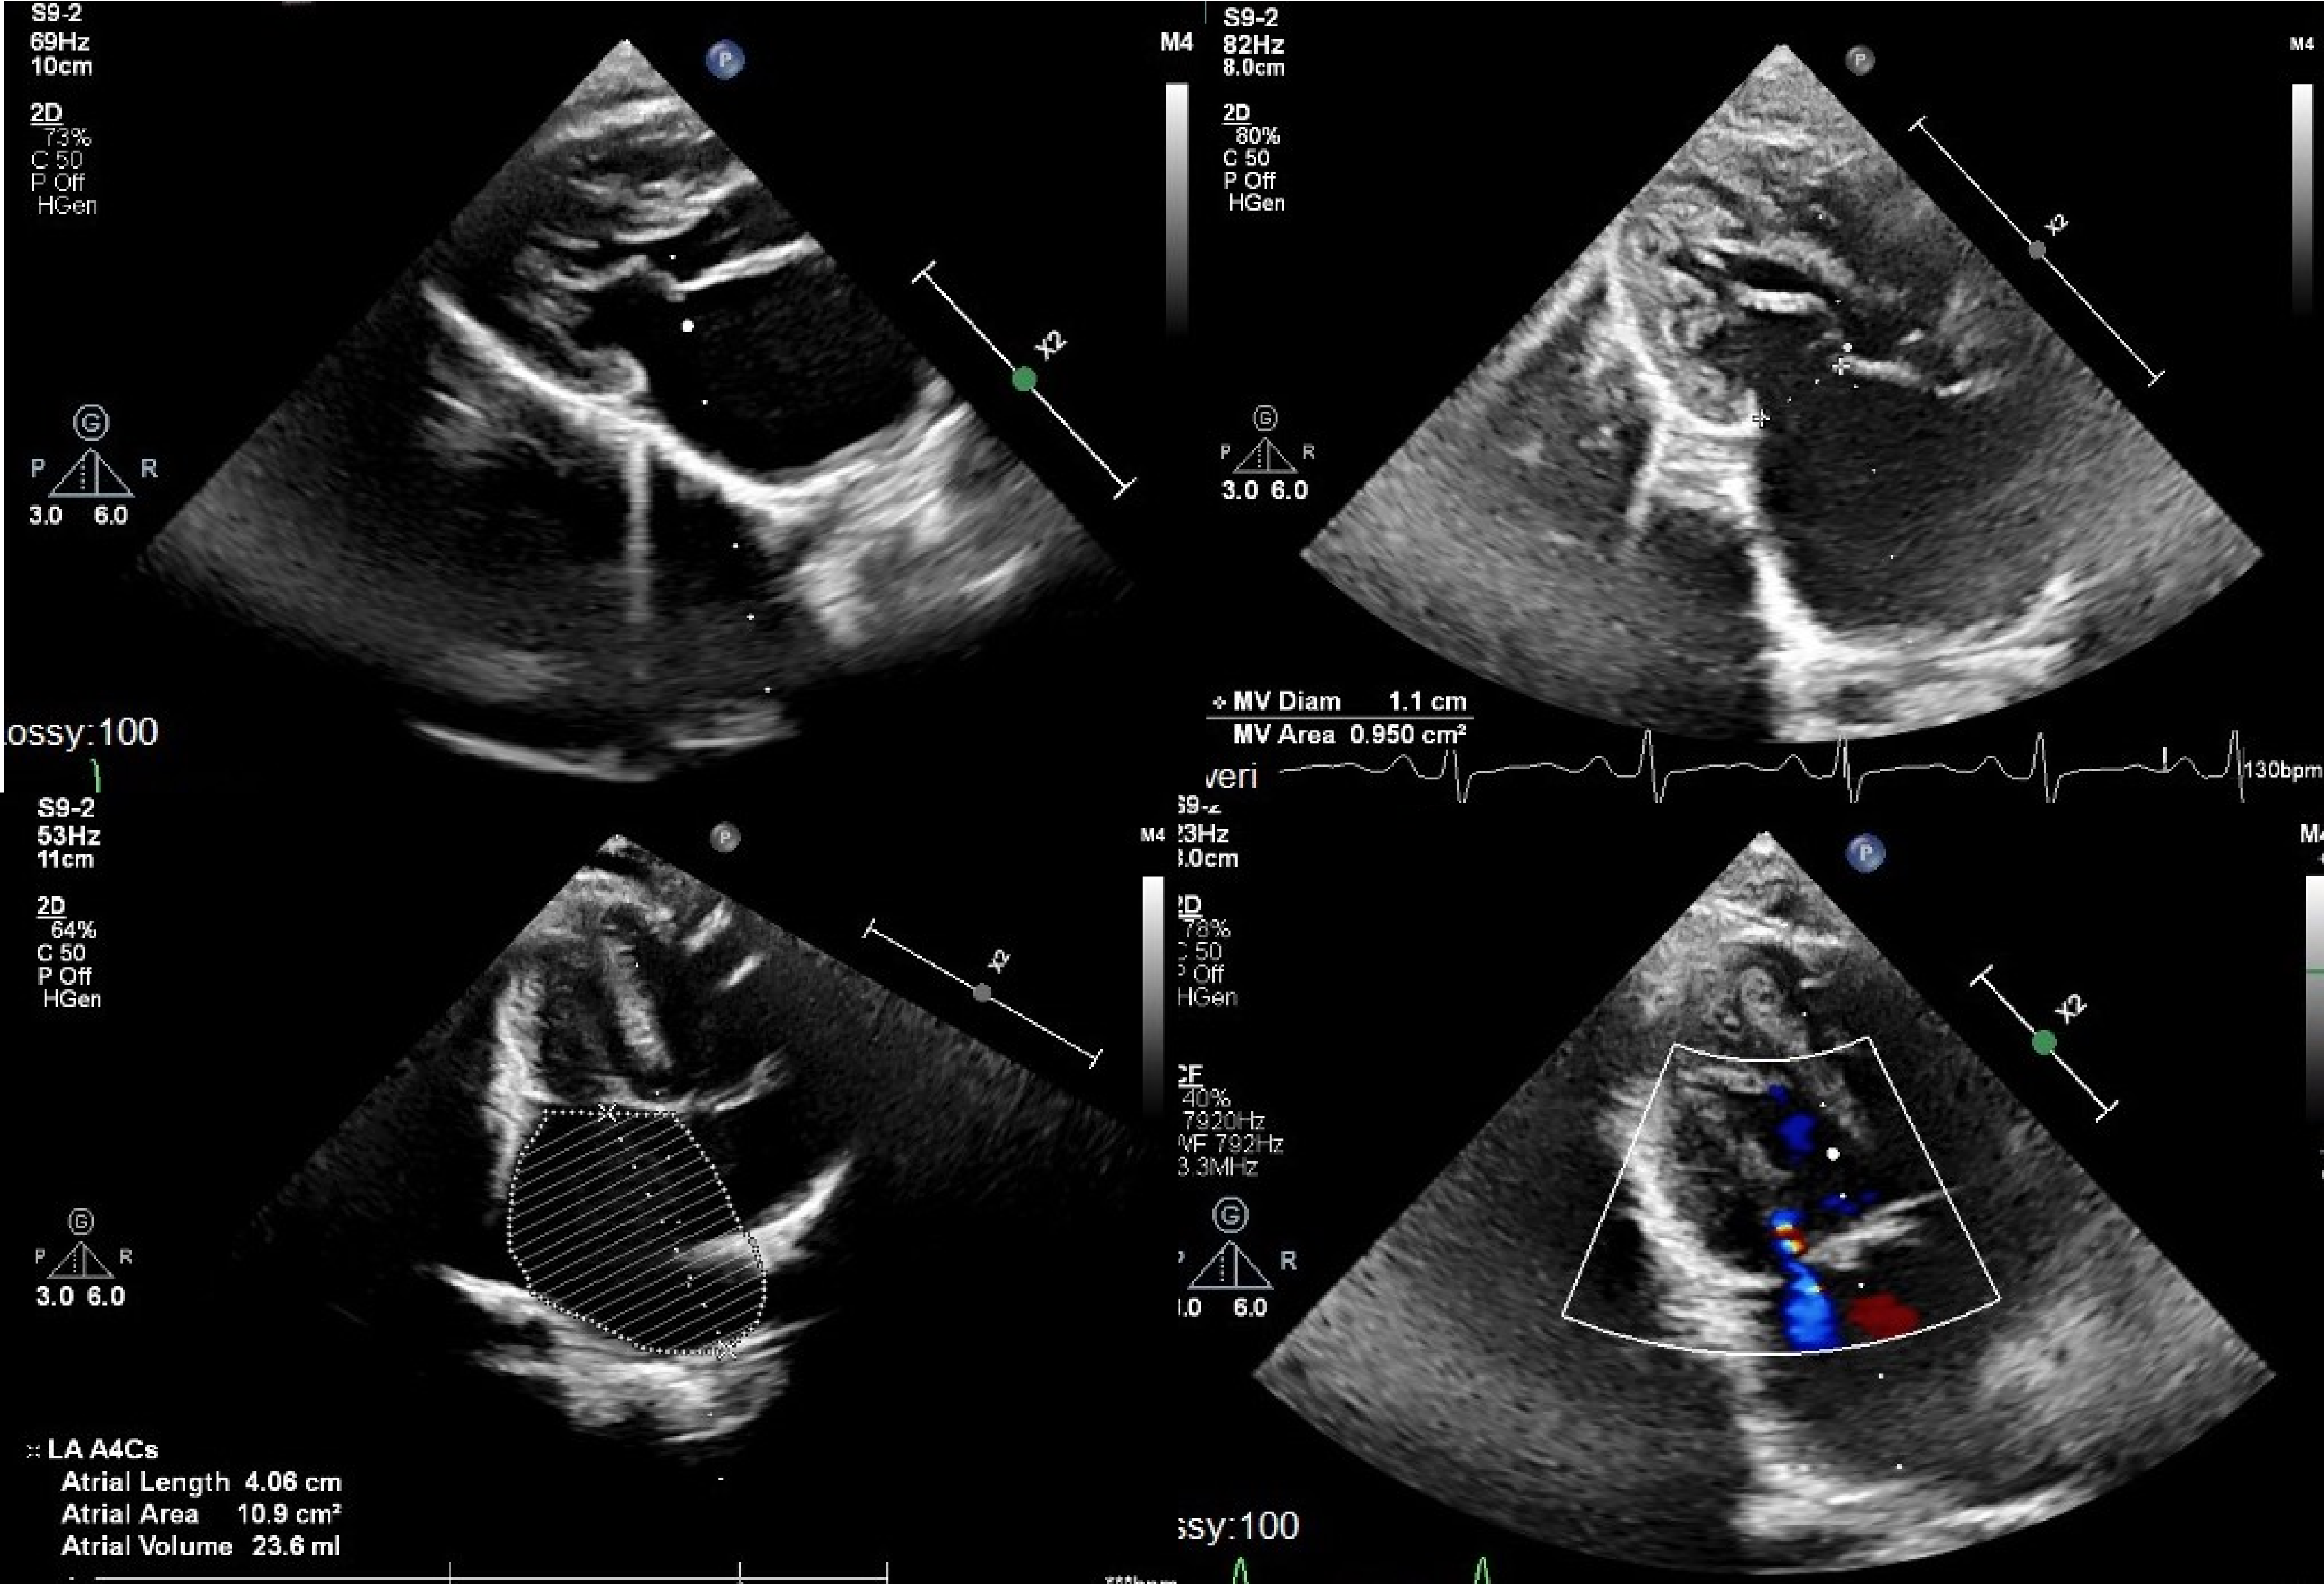

A 15-month-old male weighing 6.5 kg was referred for shortness of breath and tachypnoea. History revealed that patient was diagnosed with Kabuki syndrome. Patient was found to be tachycardic and tachypnoeic at examination. On the chest X-ray, pulmonary congestion and enlarged left atrium were evident. Electrocardiogram showed P-mitrale pattern, suggestive of left atrial enlargement. Echocardiography showed normal left and right ventricular systolic function. Left ventricle, left ventricular outflow tract, aortic valve, and ascending aorta were normal in size (z-scores of around −1). Mitral valve was stenotic with fused papillary muscles directly attached to mitral valve leaflets without distinct chordal attachments. Mean mitral inflow gradient was 17 mmHg with minimal mitral regurgitation. Left atrium was severely enlarged and right ventricle systolic pressure was measured as 65–70 mmHg. There was no other morphologic abnormality (Fig. 1). Patient was hospitalised and put on inotropes and diuretics. Because of the accompanying lower respiratory tract infection, IV antibiotic therapy was also initiated. He was discussed in paediatric heart team meeting and decision was made for mitral valve surgery.

Figure 1. Pre-operative echocardiography images showing left atrial dilatation, severe multilevel congenital mitral stenosis, and hypoplastic mitral valve annulus.